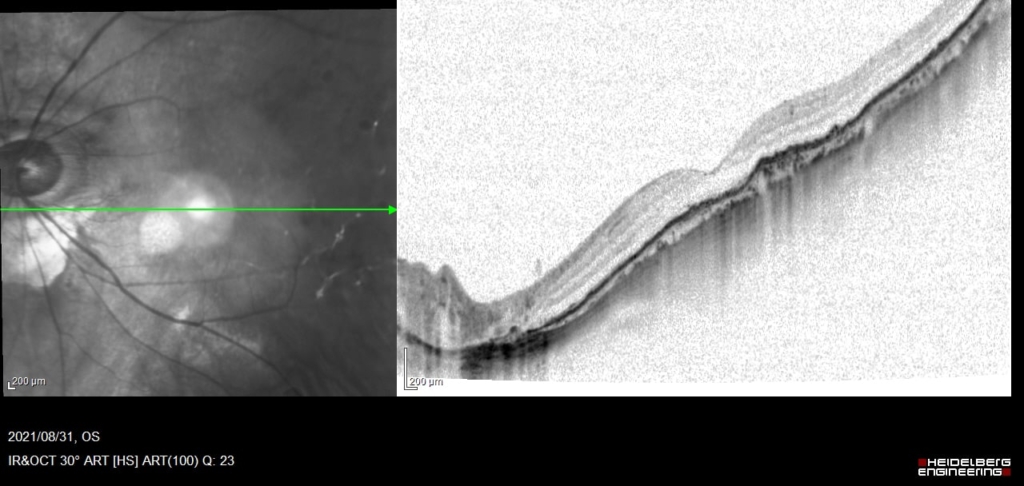

初診時

網膜下出血と出血性PEDがみられる。

低いPEDの内部は中等度~低反射が混在しており新生血管と考えられる。